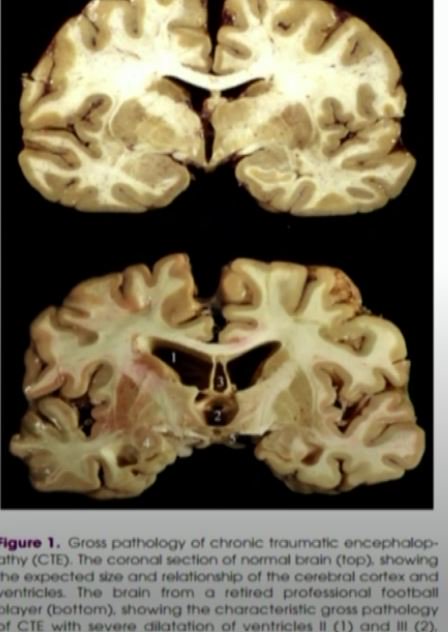

anne schindler@schindy

Chronic Traumatic Encephalophathy (#CTE) causes profound behavioral and cognitive deficits. This is the injury that plagues the #NFL Doc Wu says #DonaldSmith suffered bike accident at 9 that could have caused it @FCN2go

DWkbQ_cVQAAd2Jf.jpg

DWkbcTYVwAESZuU.jpg